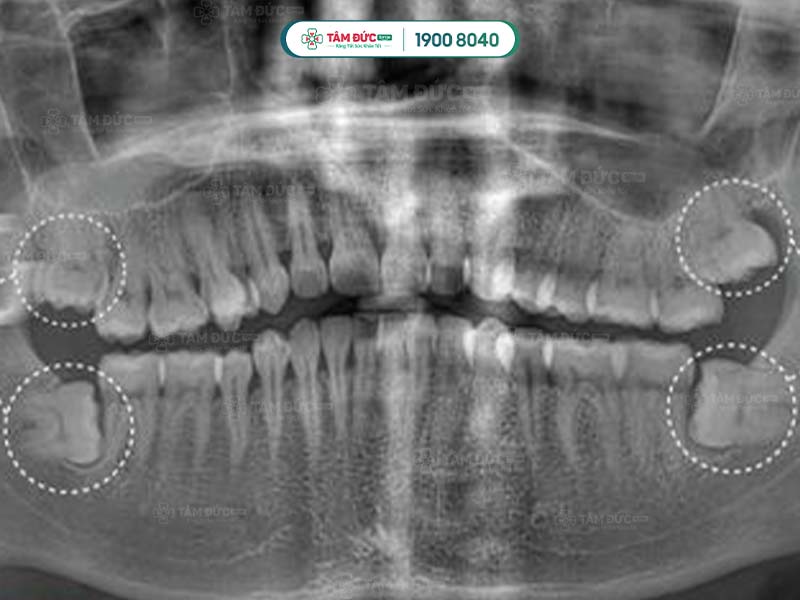

Răng khôn qua phim chụp X-Quang

Hình dạng của chân răng khôn hay còn gọi là gốc răng khôn ở mỗi người có sự khác biệt. Răng khôn có hình dáng khác với những chiếc răng còn lại, chúng hầu như có từ 2, 3 thậm chí là 4 gốc răng. Các chân này thường hợp nhất với nhau tạo thành chân lớn. Tuy nhiên, một số khác lại cuộn tròn hoặc xòe ra các hướng khác nhau.

Một số trường hợp đặc biệt, răng khôn có thể có nhiều hơn 4 chân răng. Chính vì thế, việc biết được răng khôn có mấy chân là điều cần thiết giúp bác sĩ lựa chọn giải pháp nhổ răng khôn an toàn nhất.

Răng khôn thường mọc ở phía sâu trong khoang miệng, sau răng hàm thứ 2. Răng khôn thường mọc ở 4 vị trí góc miệng: hàm trên trái, hàm trên phải, hàm dưới trái và hàm dưới phải.

Một số ít trường hợp, răng khôn không mọc ở cả 4 vị trí. Có người chỉ mọc 2 chiếc, có người chỉ mọc 1 chiếc. Quý khách không thể tự đếm hay nhìn thấy răng khôn mọc ngầm bằng mắt thường, mà cần phải thông qua chụp phim X-Quang.

Đầu tiên là bước thăm khám lâm sàng để thu thập những chỉ số cần thiết như: chỉ số đông máu, số lượng tiểu cầu… Tiếp đến, Quý khách sẽ được chụp X-quang nhằm xác định răng khôn có mấy chân và hình dáng của chân răng khôn.

Sau khi nhận kết quả chụp phim, bác sĩ tiến hành đánh giá tình trạng và độ khó của phẫu thuật. Tiếp đến, Quý khách sẽ được tiêm thuốc gây tê tại chỗ. Với trường hợp răng khôn dễ nhổ: bác sĩ tiến hành rạch trên nướu, làm sạch vùng phẫu thuật để tiếp cận và nhổ bỏ răng khôn. Trường hợp khó hơn: răng khôn có nhiều chân thì cuộc phẫu thuật có thể kéo dài. Lúc này bác sĩ sẽ rạch và cắt từng chân của răng khôn để đảm bảo an toàn.